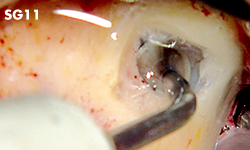

Sinus graft

Flat circular convex elevator / Angled at 90°

Flat circular convex elevator / Angled at 135°

Cone compressor

Sinus membrane

Sinus graft